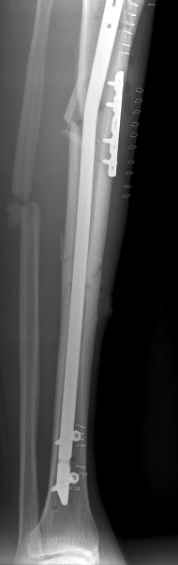

The tibia shaft fracture (proximal 1/3 of the shaft) is apex medial 20 degrees, slightly short and a few degrees apex anterior after nailing. The nail extends quite proximal to the entry site. I wasn't able to see the distal end of the nail on my screen and am not certain if there was distal locking.

Simon Reuben 18 Декабрь 2003, 17:17

Current situation is unacceptable.

1 medial entry point

2 overriding fracture in valgus.

3 proximal locking bolt missing the static locking hole. Or maybe a poller screw!?

4 the Nail is not too long. in fact it maybe too short once fracture reduced and nail fully inserted distally!